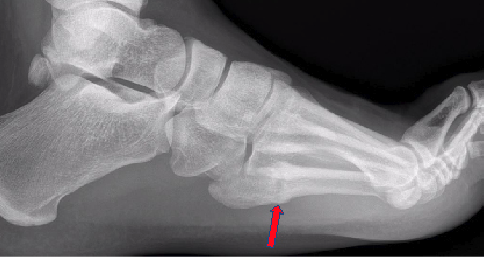

It is important to recognize the age of the fracture. I have noted radiologists routinely mistaking acute fractures for stress fractures based on location. I’ve heard surgeons tell patients that their fracture isn’t healing based on a 6-week-old injury, due to signs of bone resorption, which is normal sign of healing. Unfortunately, not all Jones fractures get X-rayed the same week, let alone within a month of the injury, so they may present already showing signs of radiographic healing. Either way, I find it is common that one may overread the imaging. See Figures 2-3.

Any screw utilized should have intramedullary purchase. Far too often in athletes, I find this does not happen. I also find screws of 4.5mm or greater are best, depending on the width of the metatarsal shaft. With digital radiology systems, surgeons can pre-plan and measure the canal in at least 2 views to ensure adequate intramedullary purchase. See Figure 4.

Keep the screw length as long as you can, unless you have a plantar curve on the lateral view. In my observation, too long a screw will distract the fracture with cases that have a plantar curve. Average screw length range from 50-55mm, in my experience. See Figure 5.